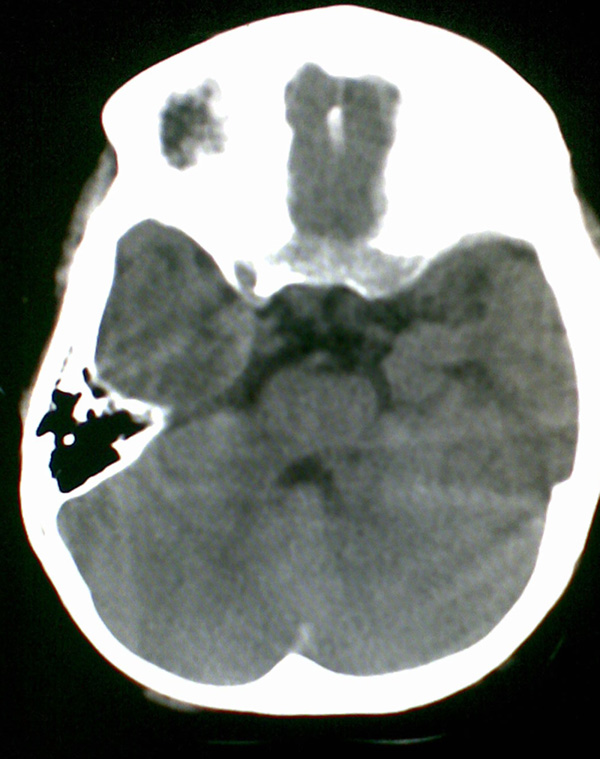

男4岁,反复抽搐多年,今早再次大抽搐,伴昏迷

1)右侧大脑半球大面积脑梗塞。2)双侧额叶脑软化灶。3)脑萎缩。

建议:必要时行dsa检查排除烟雾病可能。

右侧大脑半球大面积脑梗塞。双侧额叶脑软化灶。考虑血管畸形继发,建议进一步检查。